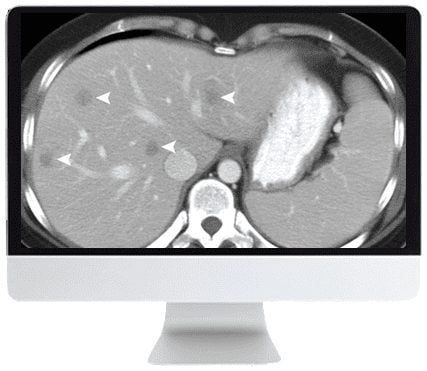

Composed of abdominal radiologists with subspecialty expertise in each cancer type, the Society of Abdominal Radiology’s Disease-Focused Panel has worked alongside clinical counterparts in surgery and oncology to develop standardized guidelines for image acquisition and exam reporting. Focused on diagnosis, treatment, and surveillance, this Online Course will present a multidisciplinary consensus for imaging hepatocellular, pancreatic, ovarian, and prostatic cancers, as well as the 2019 Bosniak classification of cystic renal masses.

- Describe hepatocellular carcinoma and pancreatic adenocarcinoma CT and MRI after therapy.

- LI-RADS Treatment Response Algorithm: Unequivocal Updates—M. Mendiratta-Lala

- Pancreatic Ductal Adenocarcinoma: Posttreatment Imaging and Reporting Updates—A. Kambadakone-Ramesh